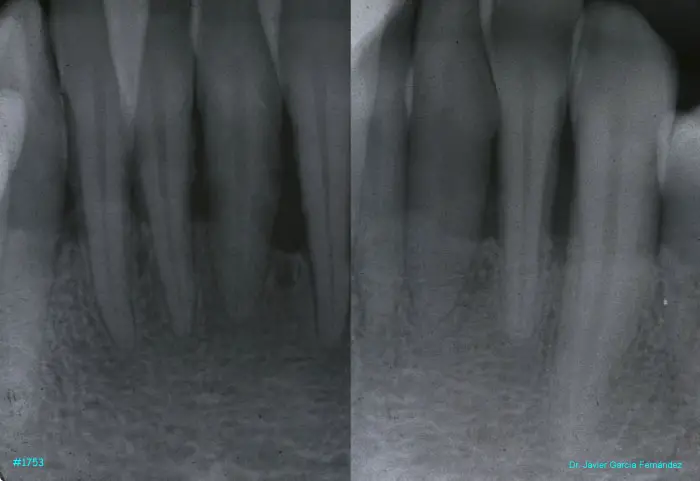

image 21